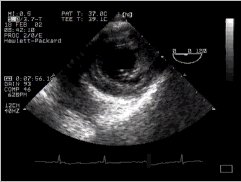

9. Main pulmonary artery (with RPA) - 'ME Asc Aortic SAX'

10. UP Basal view - main pulmonary artery CLICK FOR VIDEO: main pulmonary artery (basal)

MPG  MPG4  QT  Real

These views are of the main pulmonary artery at the level of its bifurcation. See how the origin of the right pulmonary artery is visible (rpa), but note the position of the left main bronchus (lmb) in the image - even if you move cephalad and rotate the probe, to try and visualise the left pulmonary artery, it will be obscured by this bronchus!